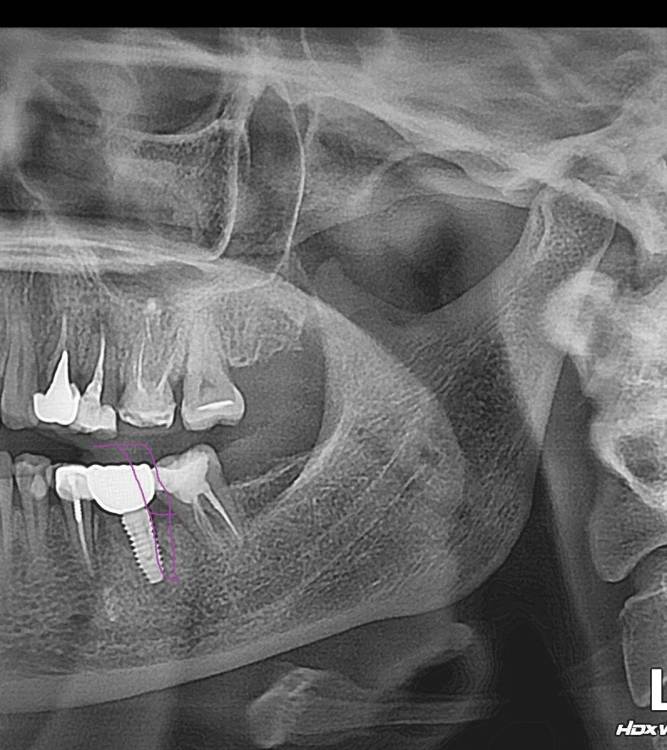

руслана Опубликовано 27 февраля, 2024 Поделиться Опубликовано 27 февраля, 2024 Здравствуйте. Какие варианты лечения? оголился имплант 1мм ( доктор сказал абатмент) коронка винтовая. установлен в 2023. Боли нет . не комфортно. Возмож но ли удаление если интегрирован хорошо. Пластики десны и посадка кости при имплантации не предлагалась. Ссылка на комментарий

Irouil Опубликовано 28 февраля, 2024 Поделиться Опубликовано 28 февраля, 2024 На мой взгляд, решить Ваши жалобы можно только с помощью удаления импланта, переустановкой его в другое положение и последующим протезированием по интеграции Надо смотреть КТ и фото во рту, чтобы говорить точнее, есть вероятность, что после удаления импланта потребуется обширная костная пластика перед установкой нового импланта Ссылка на комментарий